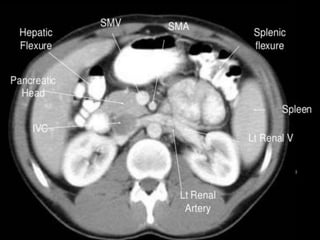

CT cross sectional

anatomy.